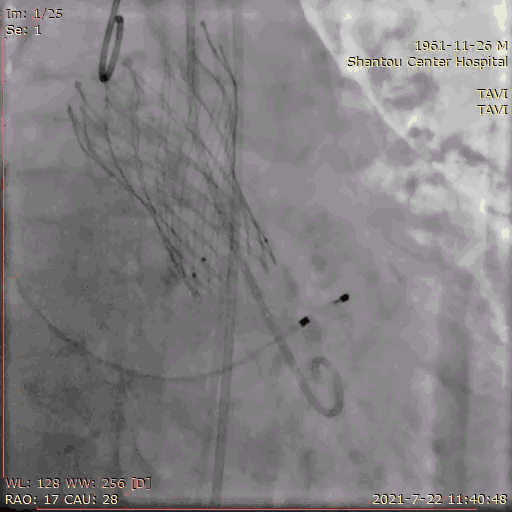

心脏角度不大,轻度钙化,左右窦黏粘;释放体位LAO 9、CRA 1;运用cusp-overlap技术定位角度;RAO17°、CAU 28° 。

主动脉根部造影

导丝跨瓣

180bpm起搏后打球囊,造影,撤球囊,停起搏;22球囊预扩后,观察到无反流,左右冠脉通畅。决定使用26号瓣膜。

球囊预扩张

输送系统定位